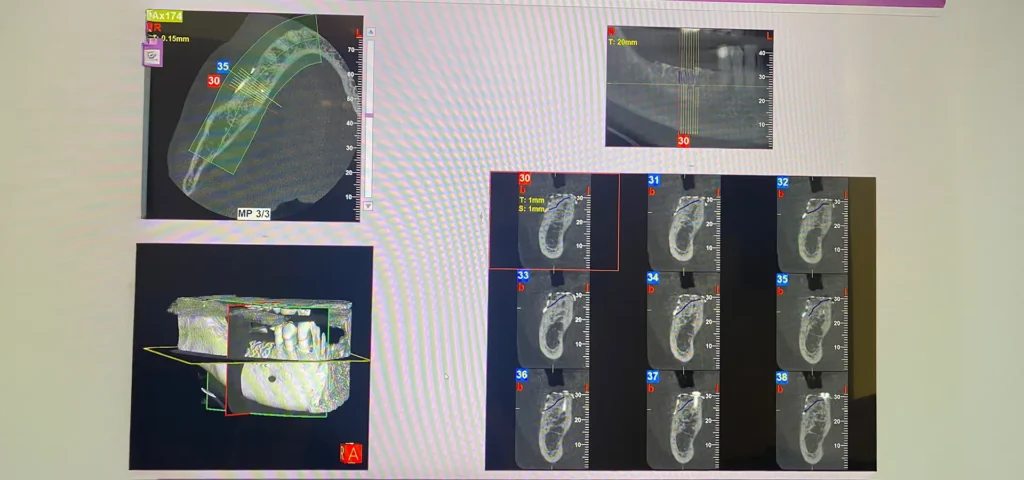

Solo una TAC Cone Beam 3D permette di valutare con precisione millimetrica l’entità della perdita ossea e di pianificare l’intervento rigenerativo più adatto.

Diagnosi Digitale 3D: La Base per una Rigenerazione Ossea Predicibile

Una rigenerazione ossea efficace e sicura nasce sempre da una diagnosi digitale accurata. La TAC Cone Beam 3D rappresenta oggi lo standard diagnostico per la valutazione pre-implantare, permettendo di visualizzare con precisione millimetrica l’anatomia ossea tridimensionale, la posizione di strutture nobili (nervo alveolare inferiore, seno mascellare, forame mentoniero) e la densità ossea.

L’integrazione tra imaging 3D e scanner intraorale digitale consente di creare un progetto chirurgico virtuale completo: attraverso software di pianificazione implantare, è possibile simulare la ricostruzione ossea, definire il volume di biomateriale necessario, posizionare virtualmente gli impianti nella posizione ideale (sia dal punto di vista protesico che chirurgico) e calcolare i tempi di guarigione previsti in base alla complessità del caso.

Questo approccio digitale offre vantaggi concreti: riduce il margine di errore chirurgico, permette di prevedere eventuali difficoltà operative, consente di comunicare al paziente in modo chiaro e visivo il piano di trattamento e, nei casi complessi, permette di realizzare guide chirurgiche personalizzate che trasferiscono la pianificazione virtuale direttamente in bocca durante l’intervento, garantendo precisione millimetrica.